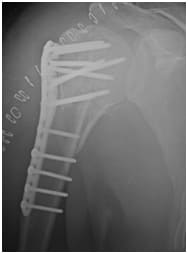

post operative X ray showing a (near!) Perfect repair!